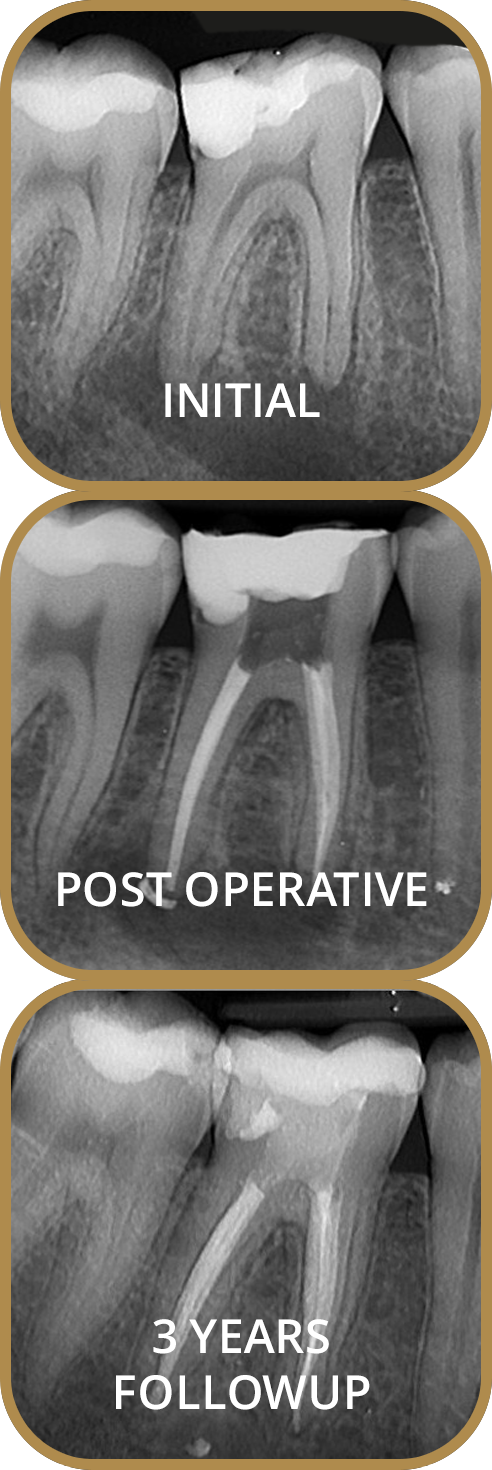

Endodontic treatment is usually referred to as root canal treatment and is carried out when the nerve inside the tooth becomes infected and causes pain. Our desired outcome for any patient is to be pain free and have healthy teeth and gums.